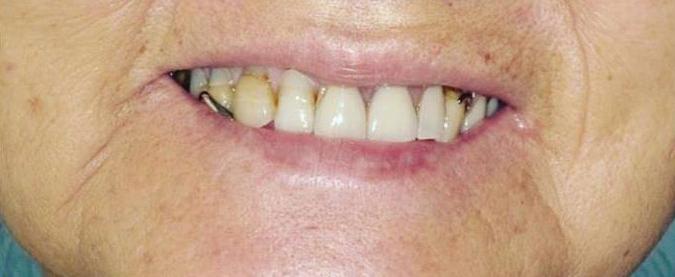

Submitted By Sivakumar Sreenivasan, DMD, MDS Dental Implant Center of Rockville

Can just four implants replace all of the teeth on the top or the bottom of your mouth? Thanks to advances in dental implant technology, that answer is a resounding yes.

Tooth loss is extremely common among adults, especially as we age. Rather than living with the discomfort and hassles of dentures, many people are opting for what is called “all-onfour” dental implant restoration.

An implant is a small titanium

screw that fits inside your jawbone and replaces the root-part of a missing tooth. Minor surgery is required to insert the implants. Once the implant is in place, a crown is attached to give you a highly realistic-looking and functional prosthetic tooth.

You do not need a dental implant for each and every one of your missing teeth. All you need is four precisely placed implants on the top of your mouth, and four on the bottom, to restore your full smile. That’s the beauty of the all-on-four. And because the implant is made of titanium, it has the unique ability to fuse to living bone and function as part of it. So eventually, the dental implant becomes part of the jawbone and serves as a strong, long-lasting foundation for your new teeth.

Besides ensuring that your implants are permanently fixed in place, this bone fusion has another important benefit: it prevents future bone loss in the jaw. This helps to maintain a more